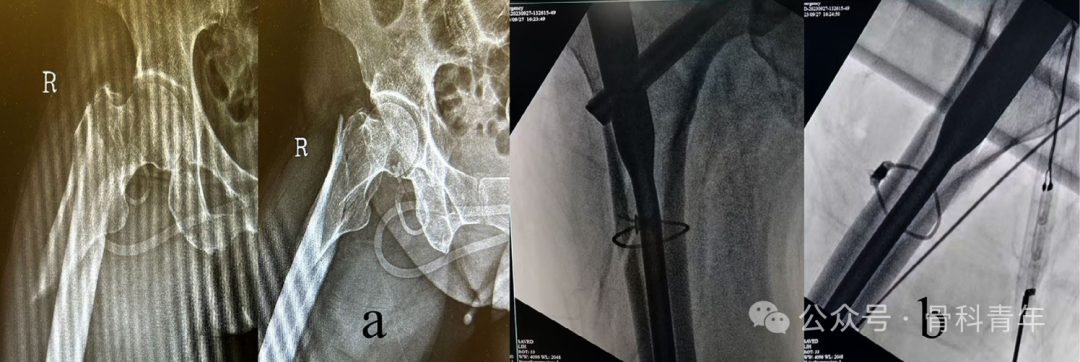

粗隆下骨折多于高暴力损伤,由于髋部髂腰肌、外展肌群的存在,骨折近端通常会存在屈曲、外展畸形,在术中牵引中,手法复位及维持复位困难。

在粗隆下骨折的复位技巧上,较为常见的有切开复位钢丝环扎,顶棒复位,或复位钳钳夹复位等:

来自西安红会医院的学者分享了一种采用血管钳微创切口辅助术中复位的方法,取得了良好的临床效果:

与传统的粗隆下骨折的牵引复位一致,先轴向牵引,后内旋内收复位,复位后可见近端骨折端屈曲外展移位: